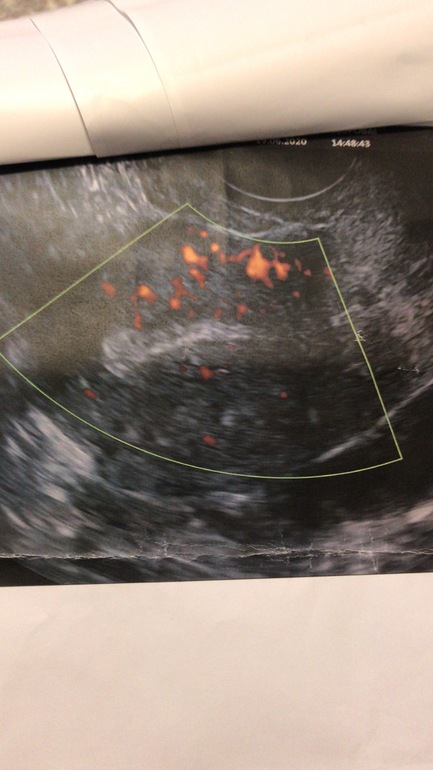

Некоторые пишут что они не помогают. Но я в них верила с самого начала. Правда долго не решалась) Но сейчас я прям обожаю их. Да ещё с таким результатом. И когда была вот последний раз на узи. Пятых сказала что у меня и количество фолликул увеличилось. Хотя в феврале ещё , она говорила что у меня иссекает запас. У меня АМГ 0,64. А тут не только кровоток улучшился но и другие показатели))))

Фото до и после